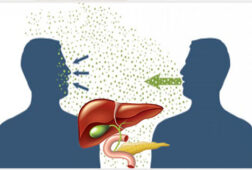

Bệnh gan có lây không? Dấu hiệu nhận biết bệnh gan

Bệnh gan có lây không là vấn đề được rất nhiều người quan tâm khi mà số lượng người mắc các bệnh về gan trong những năm trở lại đây ngày càng tăng cao. Kể tên các bệnh về gan phổ biến nhất hiện nay Gan là một bộ phận vô cùng quan trọng, ước tính gan đảm nhận g...